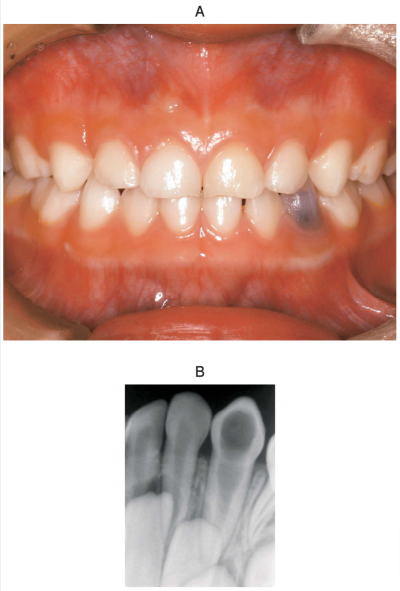

5歳の男児。下顎左側乳犬歯の変色を主訴として来院した。6か月前に気付いたが、そのままにしていたという。初診時の口腔内写真とエックス線画像を別に示す。

原因として考えられるのはどれか。1つ選べ。

c. 内部吸収